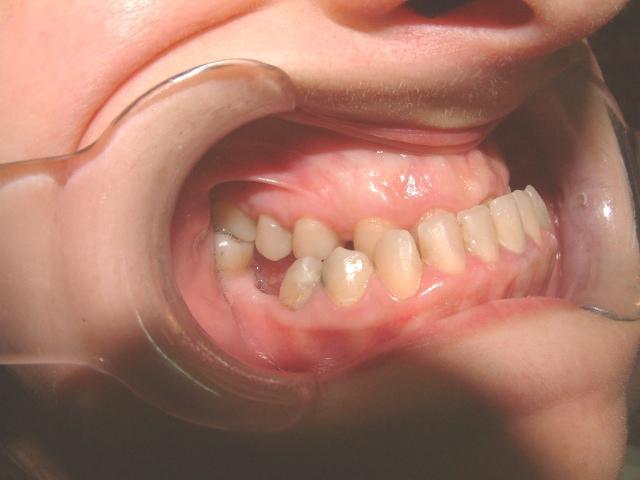

-Προγναθισμόs κάτω γνάθου

Πρώτη περίπτωση

029

Η σημασία της στοματικής υγιεινής και ορθοδοντικής πρόληψης

030

Πριν Μετά

Εάν ο προγναθισμός της κάτω γνάθου δεν αντιμετωπιστεί σε νεαρή ηλικία τότε η διόρθωση του θα χρειαστεί και τη βοήθεια της γναθοπροσωπικής χειρουργικής, διότι όταν η ανάπτυξη τερματιστεί δεν γίνονται γναθικές αλλαγές κατά τη διάρκεια της ορθοδοντικής θεραπείας παρά μόνο μετακινήσεις φατνιακού οστού και δοντιών (19)